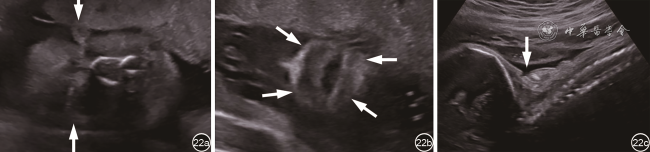

超声发现双眼前方异常低回声包块(即睑外翻)常为胎儿鱼鳞病产前诊断最具有特征性的线索。眼睑外翻时,超声声像图示胎儿双侧眼球前方显示基本对称向前突出的团状软组织低回声(图22),与后方晶状体和玻璃体无关,与眼球运动无关;正常上下眼睑闭合线消失,较大胎龄胎儿不能观察到眨眼或睁眼动作。该类胎儿的其他异常包括胎儿颜面部异常如唇外翻(大嘴)、鼻扁平,耳朵不发育或缺如;肢体异常如肢体固定,活动受限,手指足趾短,肢体姿势异常;皮肤异常如皮肤回声增强增厚或连续性中断;以及其他征象如羊水内强回声36。其中唇外翻和睑外翻是产前检出率最高的特征。该病为常染色体隐性遗传,对于有家族史或考虑该病的患儿,应建议进行与鱼鳞病相关候选基因(如ABCA12)的遗传学检查。

图22 鱼鳞病胎儿产前超声图。图a:胎儿颜面部冠状切面,可见双侧眼球前方向前突出的团状软组织低回声,双侧基本对称,并向羊膜腔突出,为眼睑外翻;图b:胎儿唇部冠状切面声像图示嘴唇增大,增厚,呈外翻状,可见舌外露;图c:胎儿背部矢状切面显示皮肤连续性中断